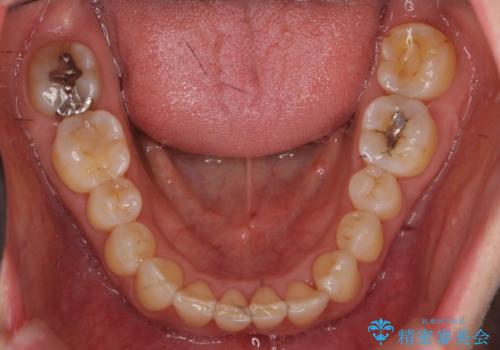

前歯が反対になっている マウスピース矯正+奥歯ブリッジ

- 前歯のがたつきを主訴に来院。

奥歯も少なく、左上奥歯はブリッジにすることになりました。

左下の前歯を中に入れるスペースを確保する目的で左下の奥歯を後ろ移動させました。

また、左下の小臼歯の捻転はマウスピースで治りにくいため、

事前にワイヤーによる部分矯正を行い、矯正用ミニスクリューを植立しています。